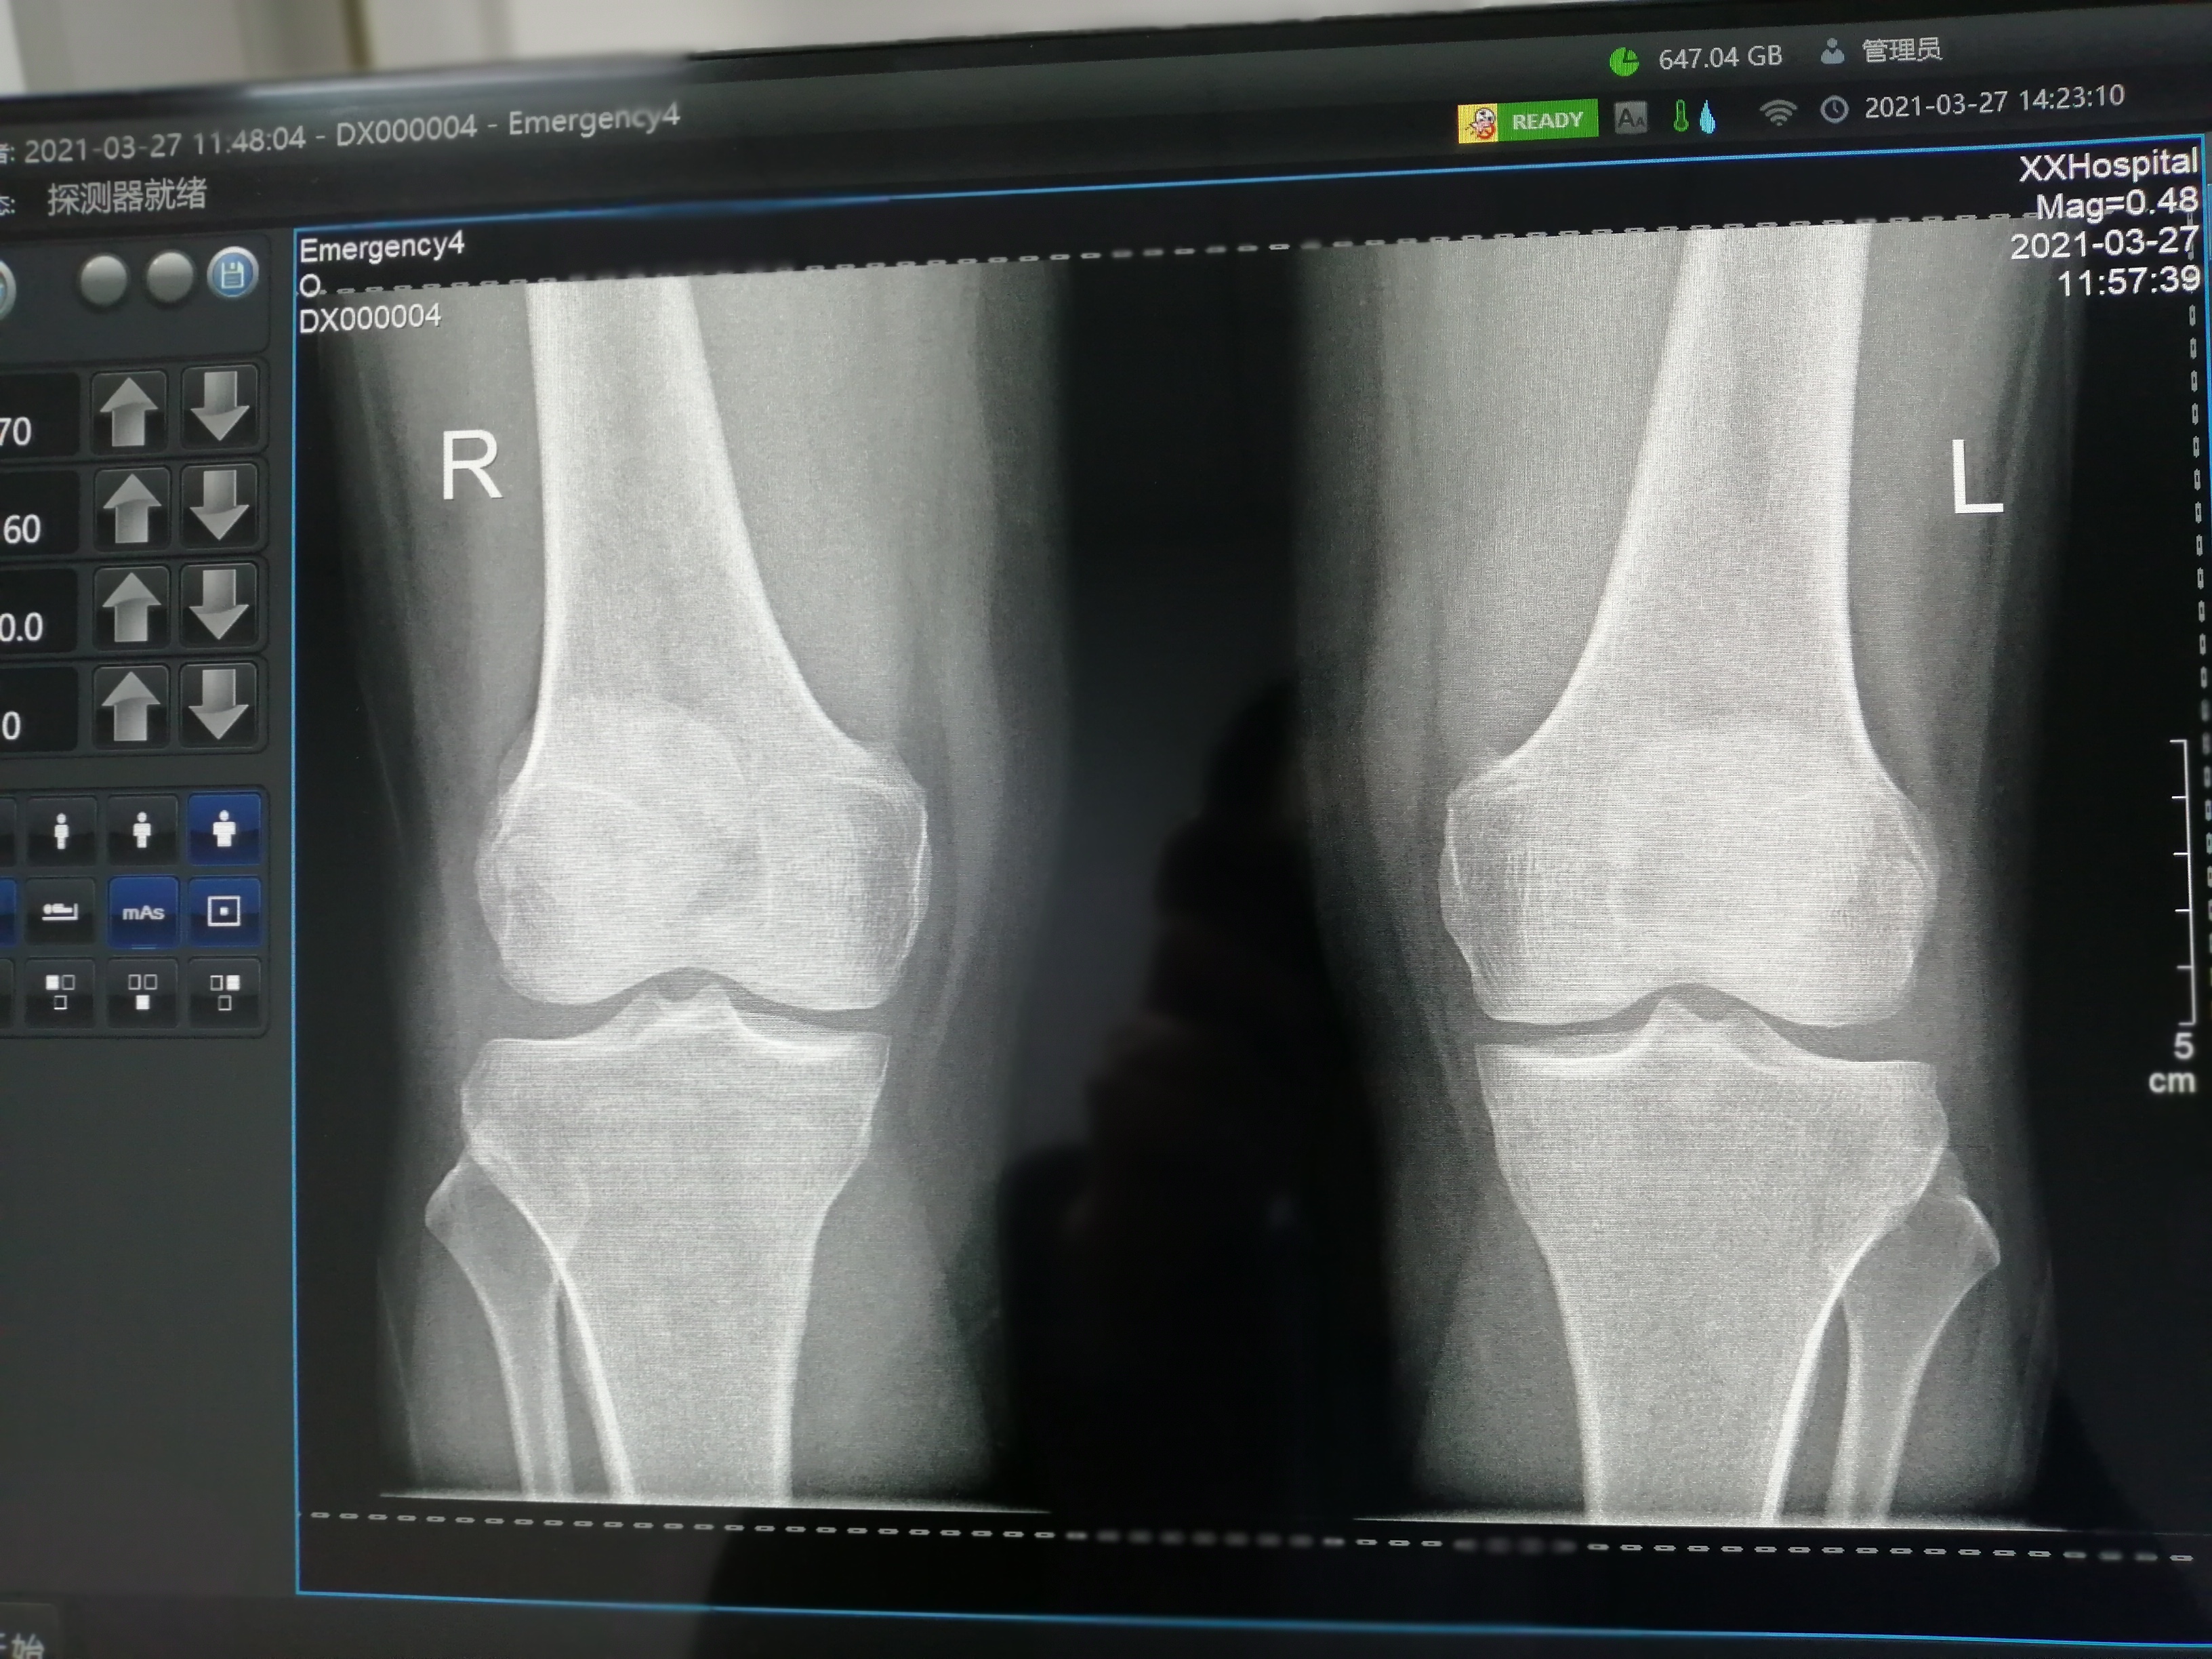

由于小焦点的曝光剂量有限,它更适合用于拍摄较薄的肢体(如四肢)和不易活动的部位(如乳突)等。在这些情况下,小焦点能够提供足够的清晰度而不需要过高的曝光剂量。